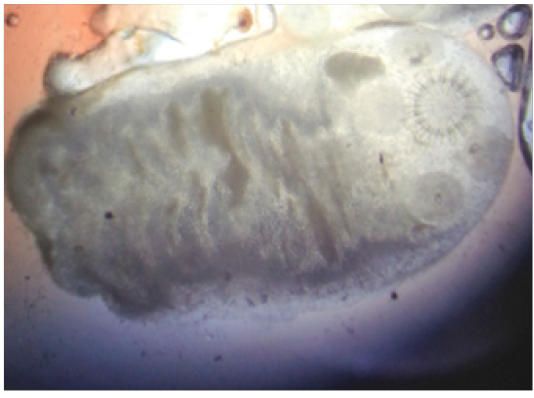

Figure 3

Microscopic view of Coenurus gaigeri showing a single scolex with hooks (10X)